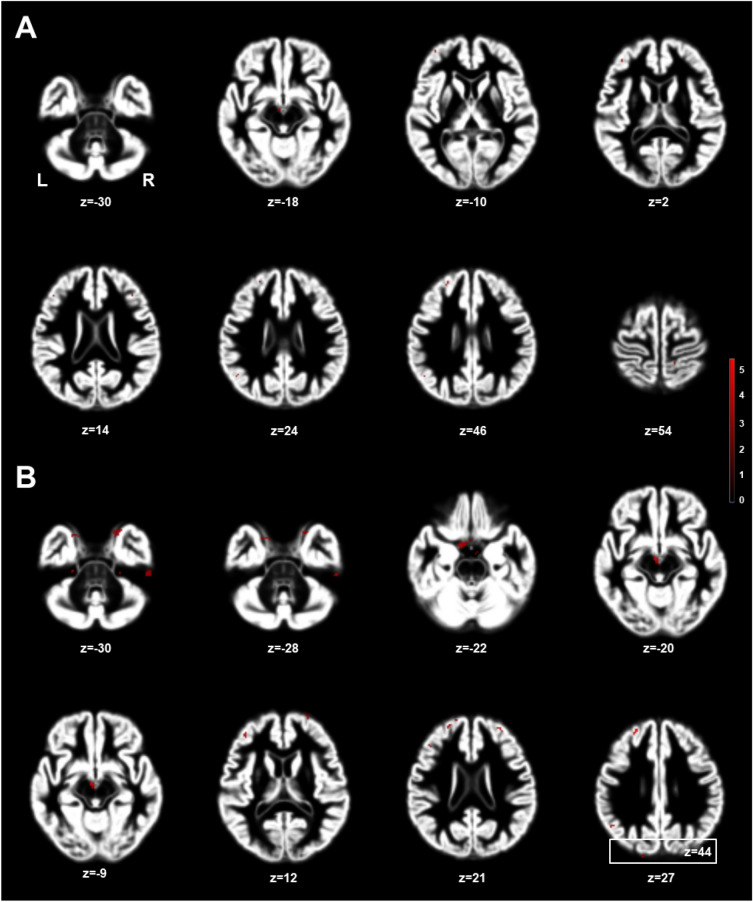

Figure 1 shows the significantly larger volumes of GM in the MHT group (cut-off t-value, 3.00; cluster size > 50) using DARTEL analysis, and the anatomical areas are summarized in Table 3. Using two-sample t-test (Fig. 1A), VBM indicated that MHT was associated with larger GM volumes in the MHT group, which included the middle frontal gyrus (MFG), hypothalamus (Hy), superior frontal gyrus (SFG), IFG, postcentral gyrus (PoG), and angular gyrus (AnG). With ANCOVA analysis adjusting for age and TIV (Fig. 1B), MHT-treated women showed larger GM volumes in the SFG/MFG/IFG, Hy, inferior temporal gyrus (ITG), parahippocampal gyrus (PHG), hippocampus (Hi), cerebellar cortex (Cb), PoG, precuneus (PCu), AnG, MOs, superior occipital gyrus (SOG), and pre-central gyrus (PrG), compared noMHT women. Figure 2 shows a bar graph in comparison of t-values using two different statistical analyses. The t-values by ANCOVA analysis were higher values than those using two sample t-test. However, there was no greater GM volume in the noMHT group.

Figure 1.

Brain areas with larger gray matter volumes in menopausal hormone therapy (MHT) women relative to noMHT women, which analyzed with independent two-sample t-test (A) and analysis of covariance (ANCOVA) (B) adjusting for age and total intracranial volume (TIV) (corrected p < 0.05; threshold t = 3.0, cluster size 50). The red color-coded pixels were scaled to the range (t-value 3.00–5.50) more than the cut-off threshold. L = left; R = right.